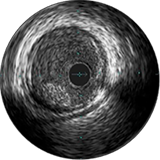

| ВСУЗИ следует использовать для диагностики стент-ассоциированных механических нарушений, ведущих к рестенозу. | IIa | C |

Усовершенствованные решения для визуализации. ВСУЗИ и SyncVision Philips:

Улучшение результатов сложных ЧКВ с помощью ВСУЗИ Фарук Джаффер, врач,